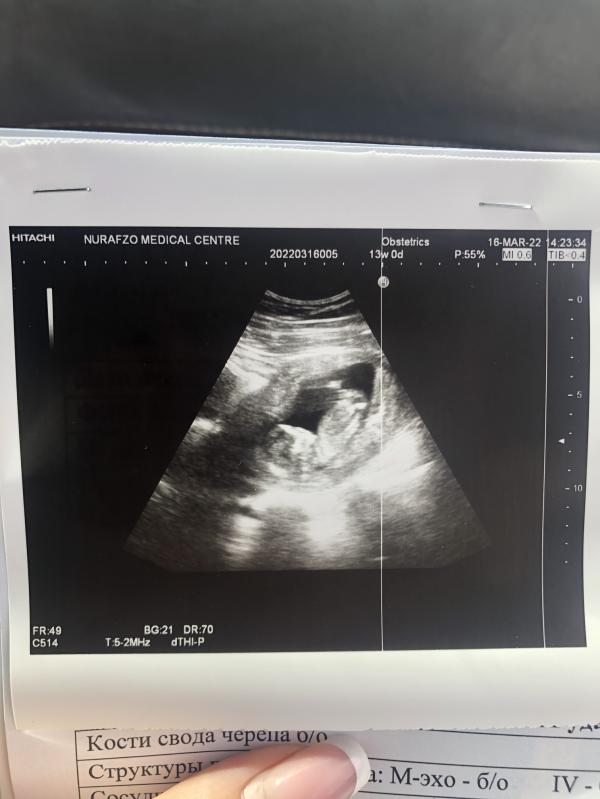

Девочки, сегодня был первый скрининг! Это лучшие эмоции. До слёз!!!❤️😍

Малышарик там такой. Сердечко стучит … аааа

Пол конечно же не сказали, сильно маленький.

Все сказали хорошо, кроме тонуса.

Прикрепляю фото. Нужны девочки ваши Советы…. У кого так было. Напугали этим тонусом страшно 😧